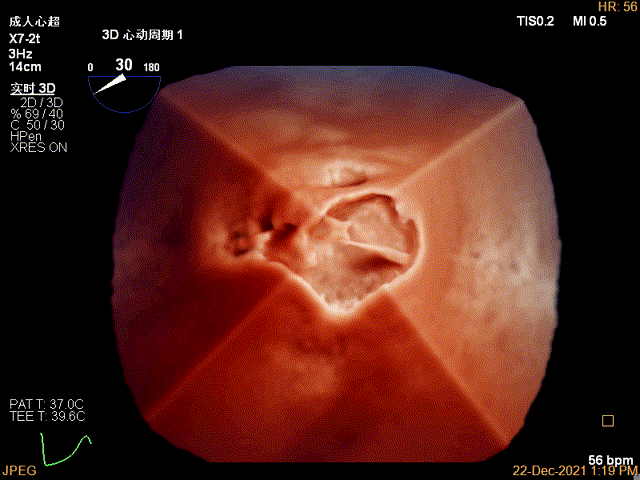

3D MV View:P2区脱垂

TEE Bicom view:二尖瓣后叶P2区大范围脱垂,部分累及1区及3区

Color-view:极大量反流,主要来源于2区